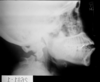

18

ignore arrow

A

Axial compression

Halo brace (post halo reduction)

unstable fracture